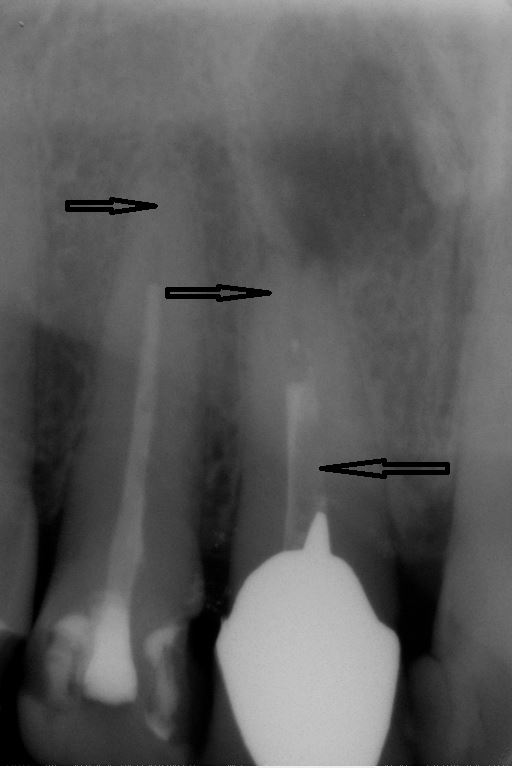

Fallbeispiel für einen Seitenrand

Fallbeispiel für einen komplexen Kanalverlauf

Fallbeispiel für eine große Entzündung an der Wurzel

Wurzel nach erfolgreicher Behandlung 2 Monate später schon fast ausgeheilt

Fallbeispiel für eine unvollständige Wurzelfüllung

nach Revision und dichtem Verschluss